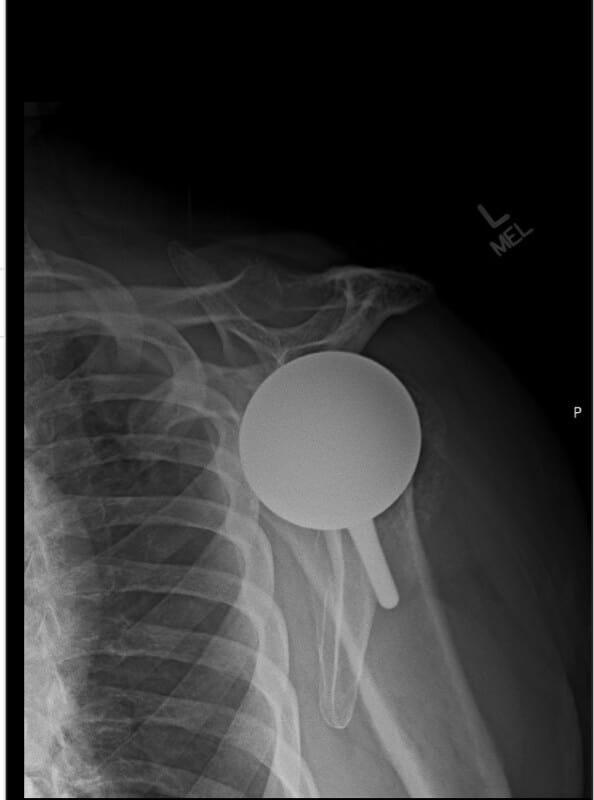

Shoulder Innovations, Inset

Selected